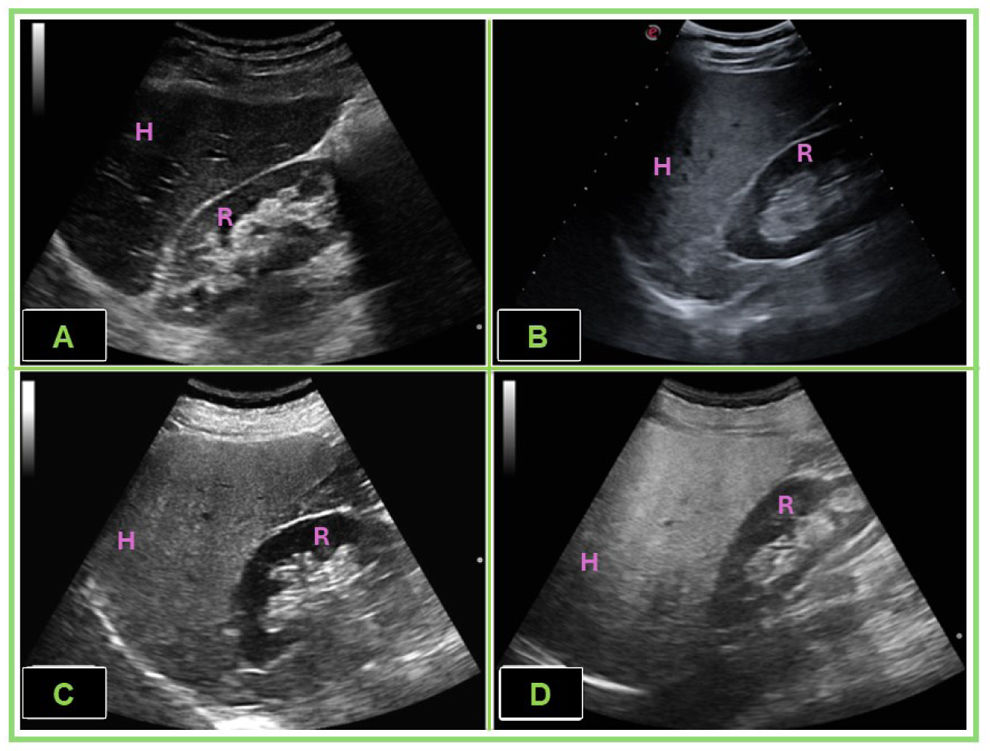

La obesidad es una enfermedad compleja y heterogénea, cuyo riesgo metabólico no depende exclusivamente del índice de masa corporal (IMC). La distribución del tejido adiposo y su funcionalidad, en particular la del adipocito blanco, condicionan la aparición de resistencia a la insulina, inflamación crónica y depósito ectópico de lípidos. La ecografía clínica permite una caracterización directa y reproducible de los principales compartimentos grasos (epicárdico, hepático, perirrenal, subcutáneo y muscular), de la grasa preperitoneal como marcador indirecto de adiposidad visceral, y de la masa muscular, superando las limitaciones de los marcadores antropométricos clásicos. Estas mediciones se han asociado con riesgo cardiovascular, disfunción renal, esteatosis hepática, fragilidad y complicaciones hospitalarias, incluso en sujetos con normopeso. Además, la ecografía permite monitorizar la evolución de estos compartimentos tras intervenciones terapéuticas. Por su accesibilidad, bajo coste y utilidad pronóstica, esta técnica representa una herramienta valiosa en la valoración integral del paciente obeso en la consulta de Medicina Interna, contribuyendo a una medicina más precisa, individualizada y eficiente.

Obesity is a complex and heterogeneus disease, with metabolic risk that is not solely determined by body mass index. The distribution and functionality of adipose tissue-particularly that of white adipocytes- play a critical role in the development of insulin resistance, chronic inflammation and ectopic lipid deposition. Clinical ultrasound enables direct and reproducible characterization of the major fat compartments (epicardial, hepatic, perirenal, subcutaneous and intramuscular), of preperitoneal fat as an indirect marker of visceral adiposity and muscle mass, thereby overcoming the limitations of traditional anthropometric markers. These measurements have been associated with cardiovascular risk, renal dysfunction, hepatic steatosis, frailty and hospital-related complications, even among individuals with normal weight. Furthermore, ultrasound can be employed to monitor changes in these compartments following therapeutic interventions. Given its accessibility, low cost, and prognostic value, this technique serves as a valuable tool in the comprehensive evaluation of patients with obesity in Internal Medicine settings, contributing to a more precise, individualized and efficient approach to care.